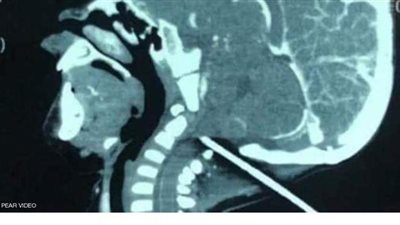

كان رضيع يبلع من العمر عاما واحدا يلهو في ساحة منزله عندما انزلق فجأة، ولسوء حظه وقع على قضيب حديدي بارز انغرز في جمجمته.